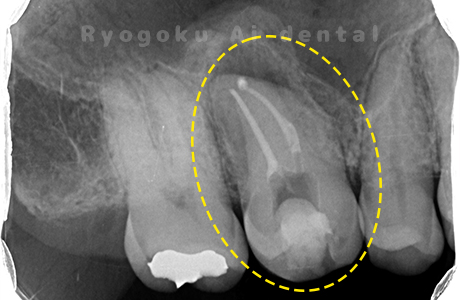

Case03

- 重度カリエス、慢性根尖性歯周炎

- 治療内容

- 自家歯牙移植

- 治療費用

- 220,000円

他院で右下の根の治療を行い、セラミックを被せる説明をされていたが、根の治療が終わらないため転院された患者さんです。隣の親知らずの抜歯の必要性と、根の治療を行なっている歯牙の予後が悪いため、移植治療を提案し、右下の親知らずの抜歯と同時に、右下の奥歯(7番)への移植治療を行いました。被せ物を行う必要もなく、順調に経過してます。

<リスク・副作用>

治療後、痛みや違和感、出血、腫れなどが出る事があります。喫煙者、糖尿病などの方の場合、歯が生着しない場合があります。